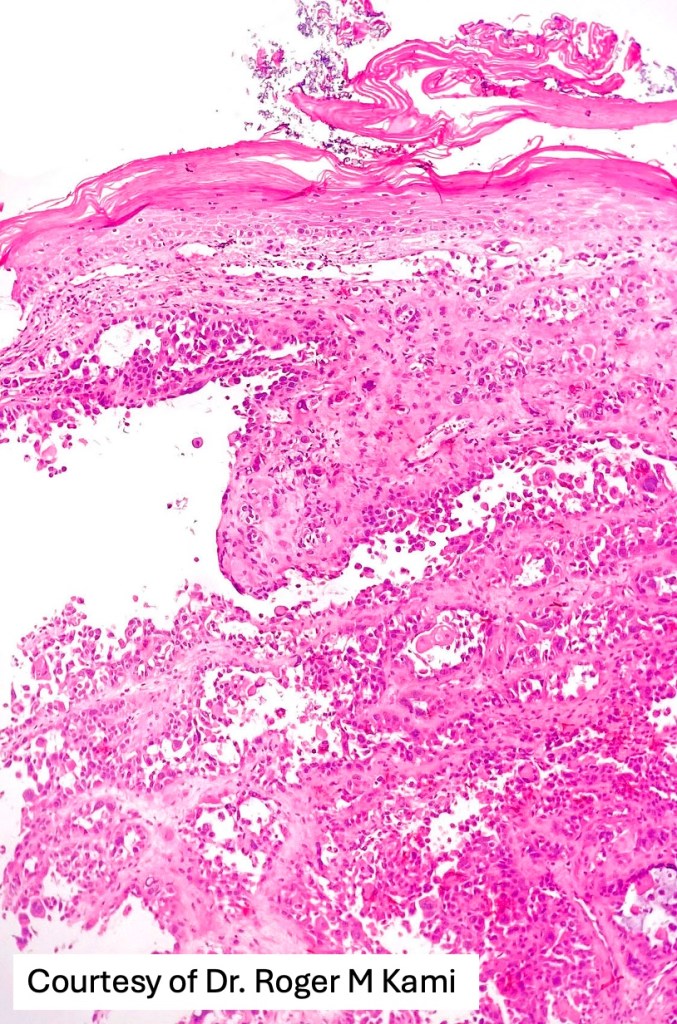

Histological features

•Acantholysis gives rise to a pseudoglandular appearance

•Often well differentiated

•Variable pleomorphism & mitotic activity